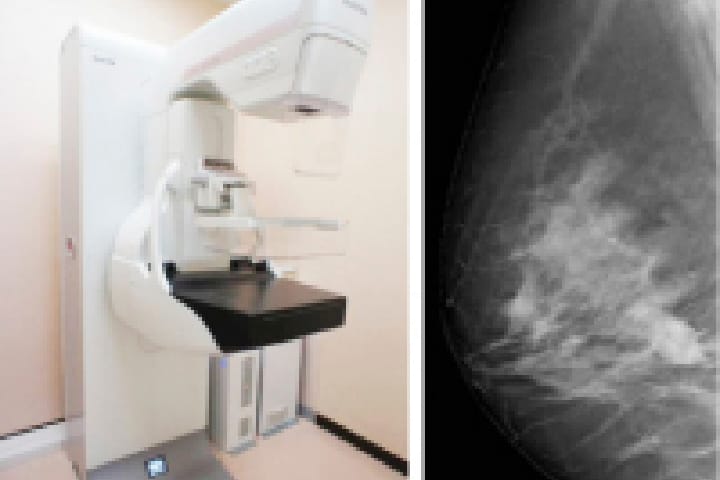

乳房専用のX線撮影装置です。

当院では、50μm直接変換方式フラットパネルディテクタを搭載したデジタルマンモグラフィ装置と、50μmFCR方式デジタルマンモグラフィ装置を用いて撮影を行います。

50μm直接変換方式フラットパネルディテクタは、直接変換方式では現在の世界最小画素サイズで、高精細で低ノイズの画像を生成します。

トモシンセシスとは「デジタルマンモグラフィ3D再構成断層撮影」のことです。

1回の撮影でX線管球が移動しながら低線量のX線をパルス状に照射し、得られた画像データを再構成して断層像を生成します。

乳房を1mm間隔の断層面で観察することができるため、従来のマンモグラフィでは乳腺の重なりのために発見が難しかった病変の観察ができ、より詳細な検査が可能となります。